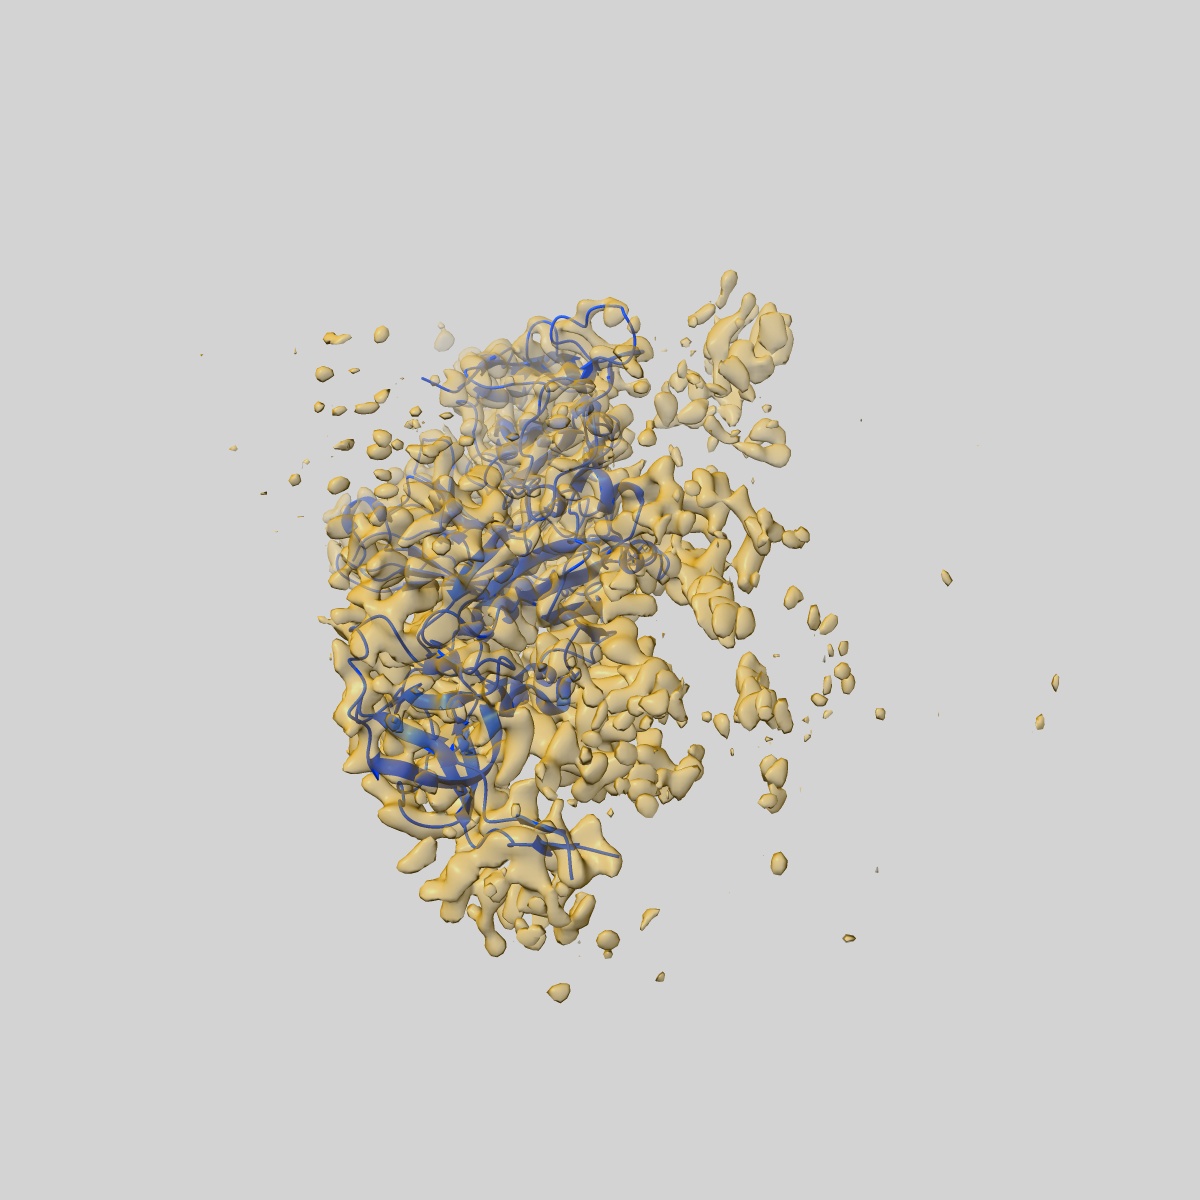

EMD-19002

XBB-4 Fab in complex with SARS-CoV-2 BA.2.12.1 Spike Glycoprotein

Single-particle3.41 Å

Sample: XBB-4 Fab in complex with SARS-COV-2 BA.2.12.1 Spike Glycoprotein

Fitted models: 8r8k